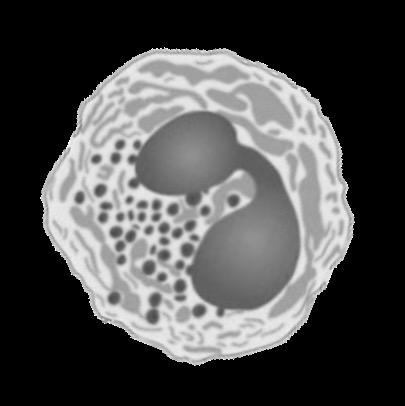

The Role of Eos in Health and Disease

Eos in Health

• Eos play multimodal roles in maintaining homeostasis1

• Eos play immunoregulatory and protective roles during parasitic/viral infections1

Eos in Disease

• Pro-inflammatory role: blood eos are increased in type 2 inflammation2

• Can result in tissue/organ damage2

• Elevated blood eos are associated with poor outcomes across multiple disease states3-5

Role of Eosinophils in EGPA Pathogenesis

Eosinophils participate in both granulomatous and vasculitic features of EGPA and cause damage through innate and antibody-dependent mechanisms.

Eosinophils release mediators, including ECP, EDN, and MBP, that contribute to tissue damage.